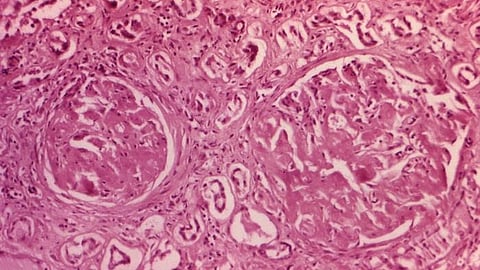

“In 2011, researchers found that some people are born with a mutation in the CYP24A1 gene, which means they cannot metabolise vitamin D properly. This causes a build-up of calcium in the blood, leading to kidney stones and kidney damage, which can be fatal in babies. It was the reason why vitamin D-fortified food in the 1930s caused intoxication in some people.

“Today, some people do not realise they have a CYP24A1 mutation until they are adults, after years of recurrent kidney stones and other problems. In most cases, these patients are screened and find out that they have the CYP24A1 mutation and the disorder now known as infantile hypercalcemia type 1, or HCINF1.